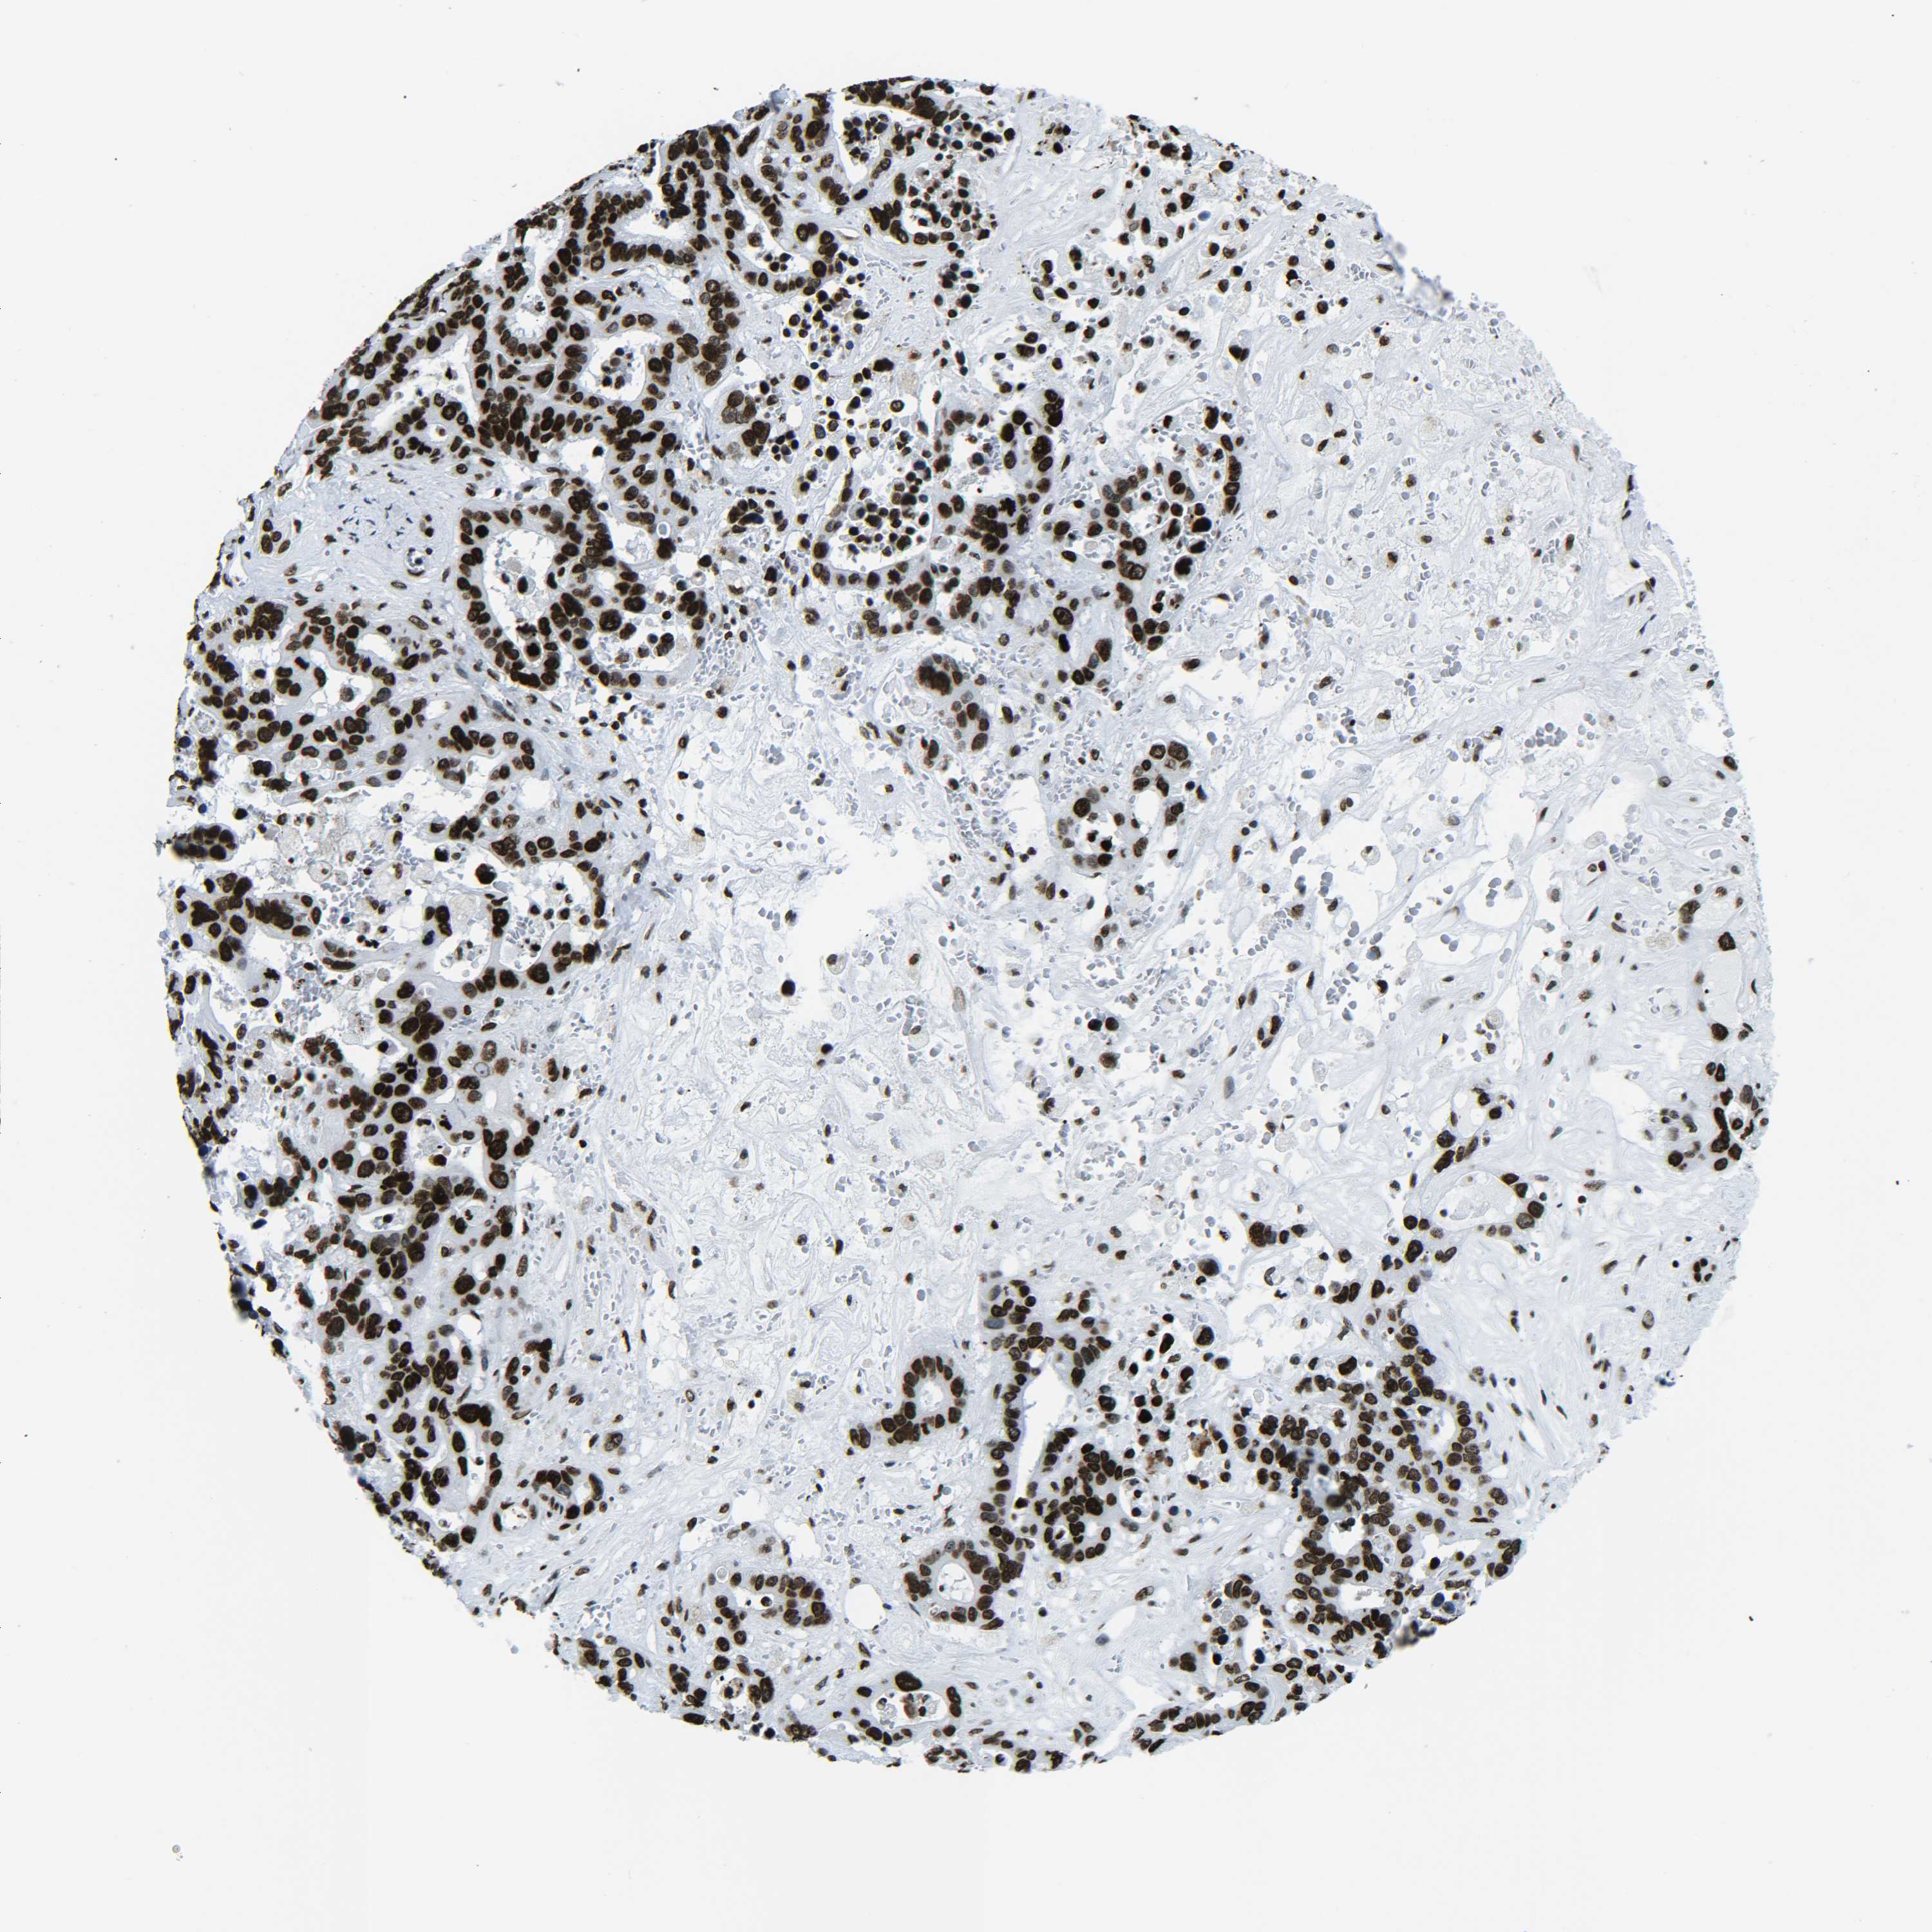

LIVER CANCER - Protein expressioni

A mouse-over function shows sample information and annotation data. Click on an image to view it in a full screen mode. Samples can be filtered based on level of antibody staining by selecting one or several of the following categories: high, medium, low and not detected. The assay and annotation is described here.

Note that samples used for immunohistochemistry by the Human Protein Atlas do not correspond to samples in the TCGA dataset.

Antibody stainingi

Antibody staining in the annotated cell types in the current human tissue is reported as not detected, low, medium, or high, based on conventional immunohistochemistry profiling in selected tissues. This score is based on the combination of the staining intensity and fraction of stained cells.

Each image is clickable and will lead to virtual microscopy that enables deeper exploration of all samples and also displays staining intensity scores, fraction scores and subcellular localization as well as patient and tissue information for each sample.

Antibody HPA041189

Antibody HPA051647

Antibody CAB012264

Staining

High

Medium

Low

Not detected

Intensity

Strong

Moderate

Weak

Negative

Quantity

>75%

75%-25%

<25%

None

Location

Nuclear

Cytoplasmic/membranous

Cytoplasmic/membranous,nuclear

Cholangiocarcinoma

Carcinoma, Hepatocellular, NOS